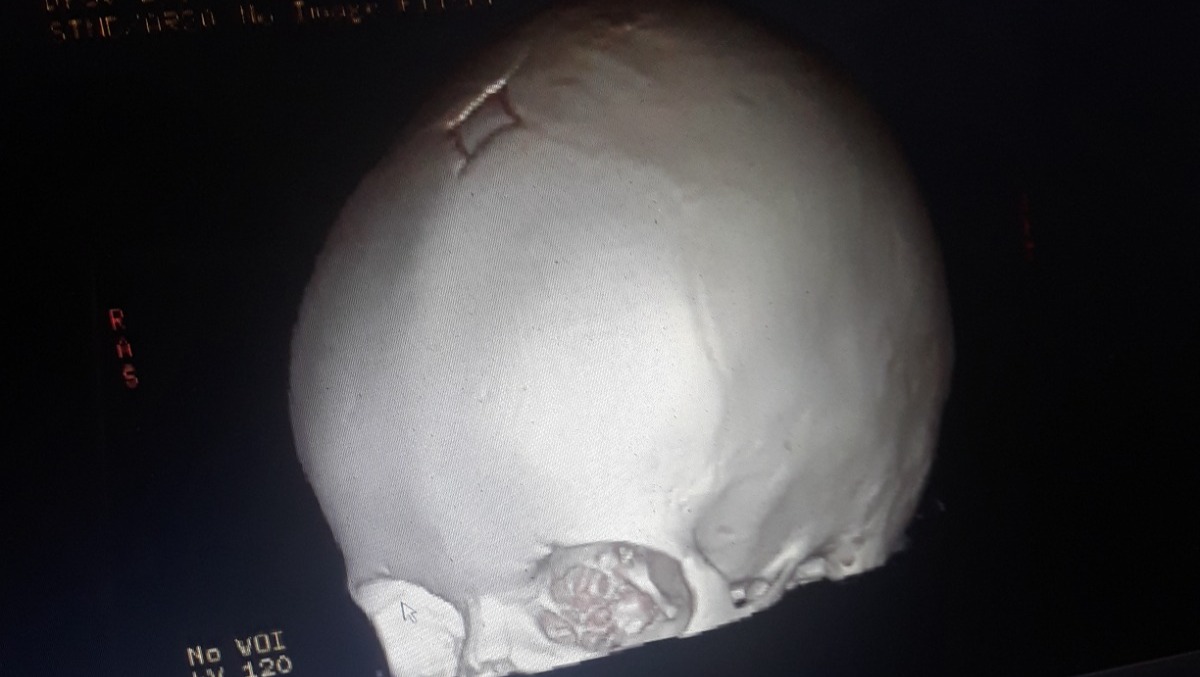

Our 15 month old Zoey LeeAnn was diagnosed with bicoronal craniosynostosis, and a simple doctor's appointment became a life changing event in the blink of an eye. After talking with the neurosurgeon and plastic surgeon we understand surgery is necessary. We find comfort in knowing God is with us  and that he gave us the very best team available Stanford has the very best facilities and doctors around. There are so many obstacles ahead that we are not prepared for. Knowing we are in the best of hands makes it a little bit easier . Zoey will be having surgery on December 17th at Lucile Packard childrens hospital at Stanford in Palo Altos California. Zoey will have pre-op appointments with her neurosurgeon plastic surgeon and the anesthesiologist on December 14th meaning we will need to fly out to California from Reno Nevada on the 12th or 13th of December. Her surgery is scheduled for the 17th and with the recovery time we believe we will be home around December 28th . We know the holidays are coming up and it's been a hard year for everybody but we are humbly asking for monetary donations to help with the costs of out of state travel, stay, food, and any unexpected cost during Zoeys surgery. Please if possible please help ease the financial stress, and allow us to focus on Zoeys surgery and recovery. And please please pray for Zoey LeeAnn she is our sweet sunflowers  brightening the day of everyone she meets. We love you Zoey LeeAnn.